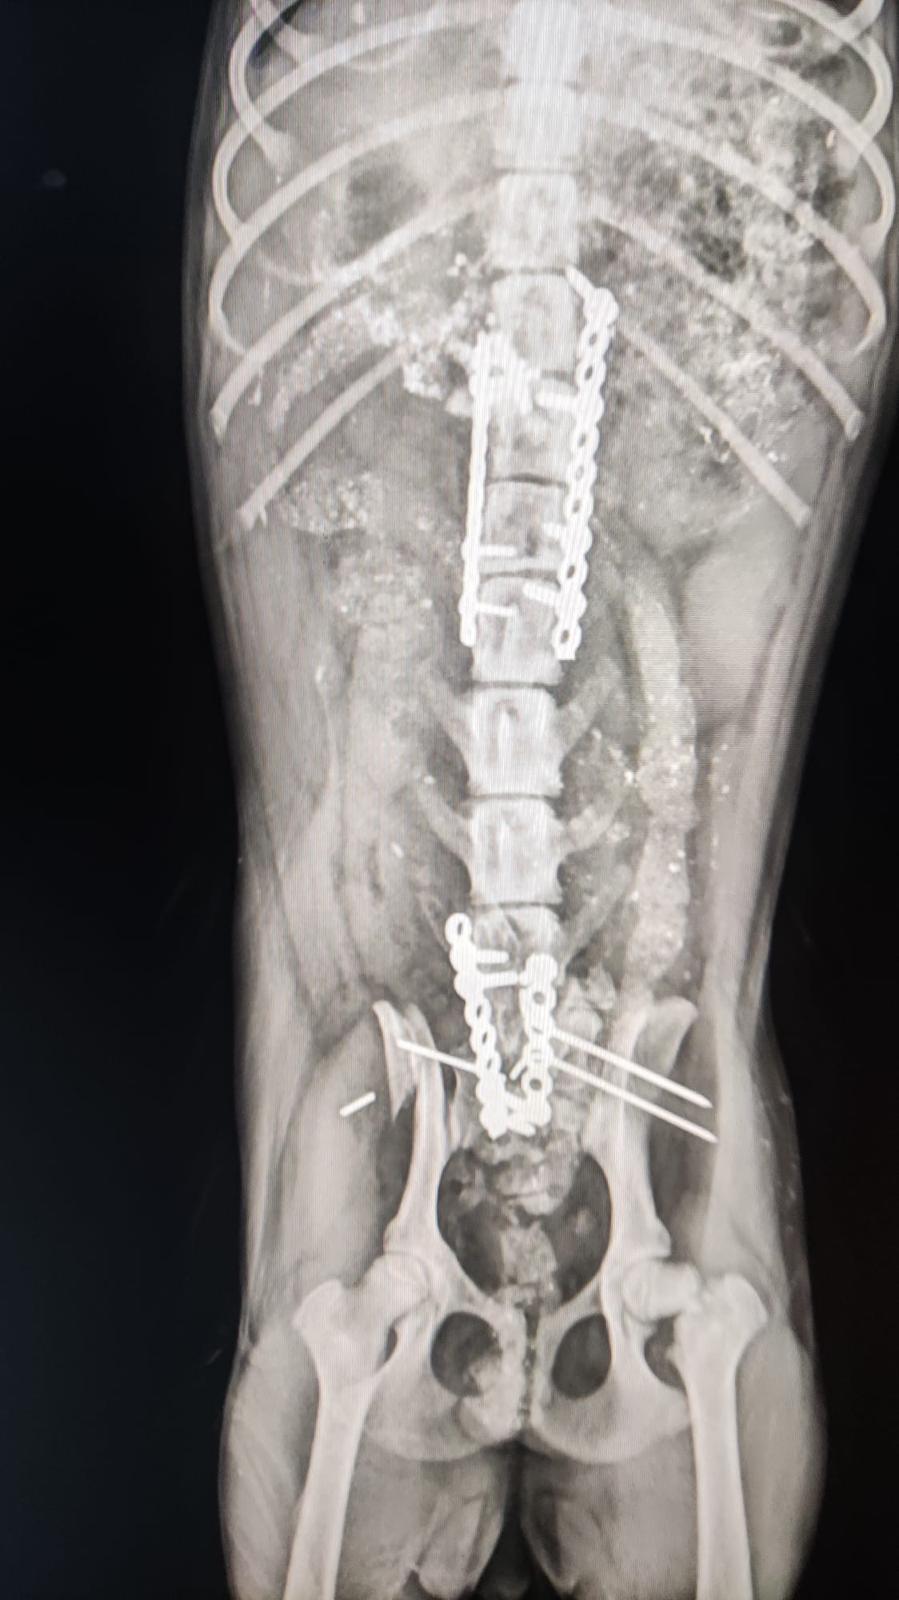

29.1.24: Leider sind die Resultate ernüchternd! Das Kleine hat vermutlich das Rückgrat gebrochen und da sind keine guten Prognosen…

Als Eva Chula in der Klinik besuchen wollte sah sie auf der Autobahn dieses kleine Wesen, das von einem Auto massiv erfasst worden war. Schnell war das ca 5,5 Monate alte Welpchen eingepackt und liegt nun in derselben Klinik wie Chula. Es muss einen massiven Schlag auf den Kopf bekommen haben und auch die Hinterbeine sind betroffen. Es muss geröntgt werden, noch wissen wir nicht, ob es überlebt…